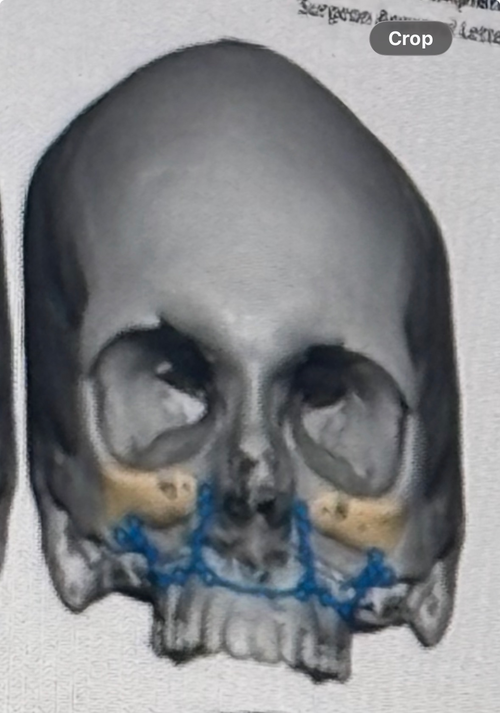

I recently underwent a Le Fort 1 with Custom Malar-Infrabortial rim implants in Boston about 2 months ago and im very happy with the results. Changed all the convexities of my face and ascended me massively. Ask me anything about the planning and recovery process